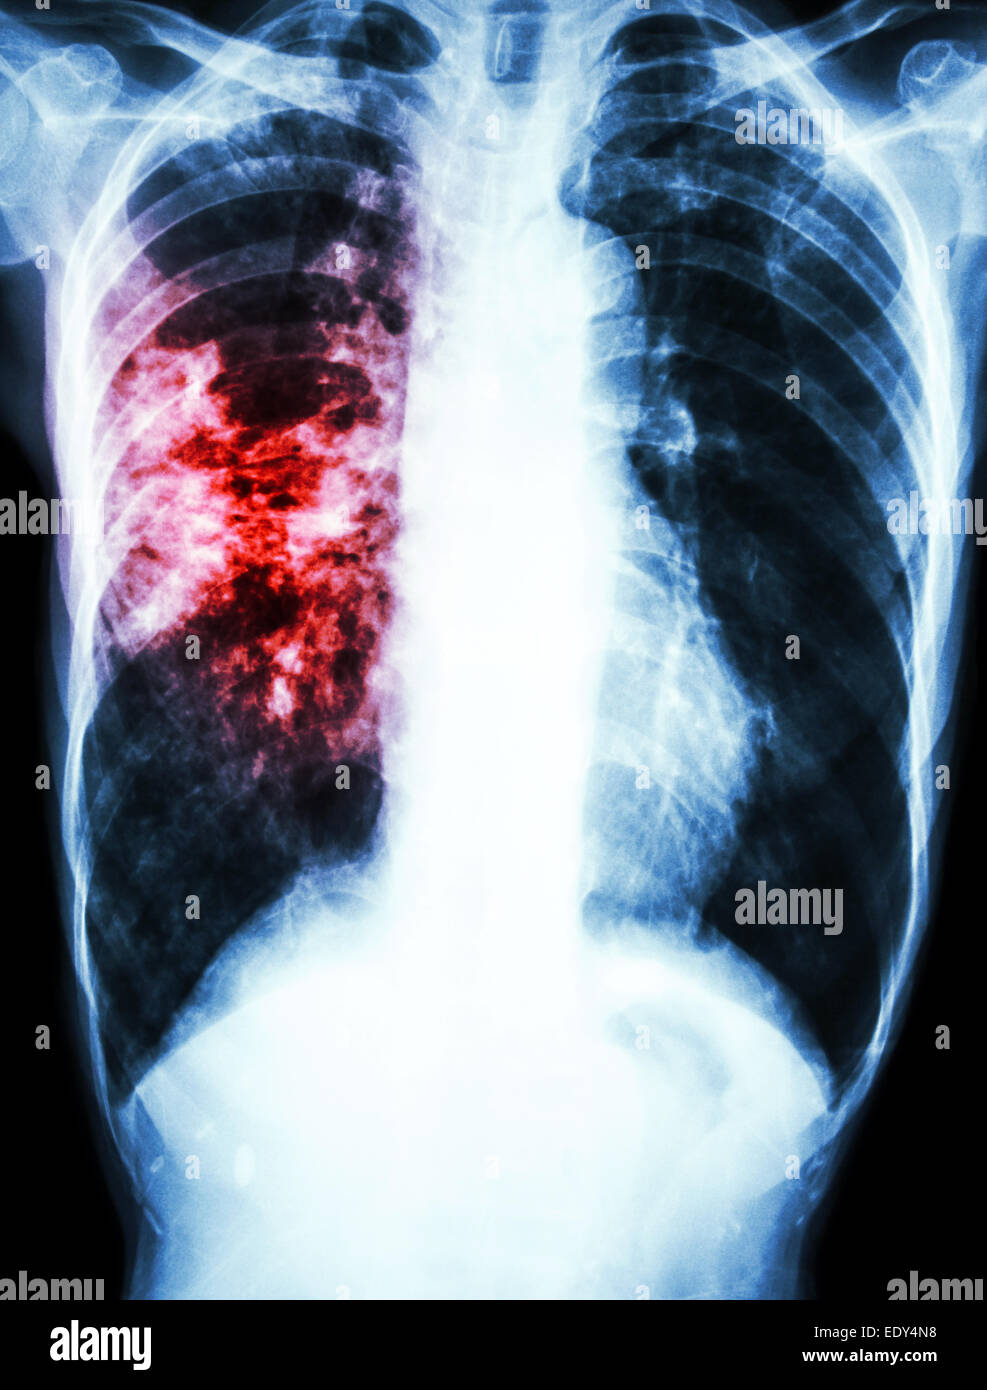

From www.alamy.com

film chest xray show alveolar infiltrate at left upper lung due to Mycobacterium tuberculosis Do Chest X Rays Show Tb Prompt diagnosis of active tb. More tests, such as a chest radiograph, are needed to rule out tb disease. In 2022, approximately 7.5 million individuals became ill with tuberculosis (tb) and 1.5 million died. Negative tb blood test or tb skin test result, but you have symptoms of active tb disease. A positive result from a tb blood test or. Do Chest X Rays Show Tb.